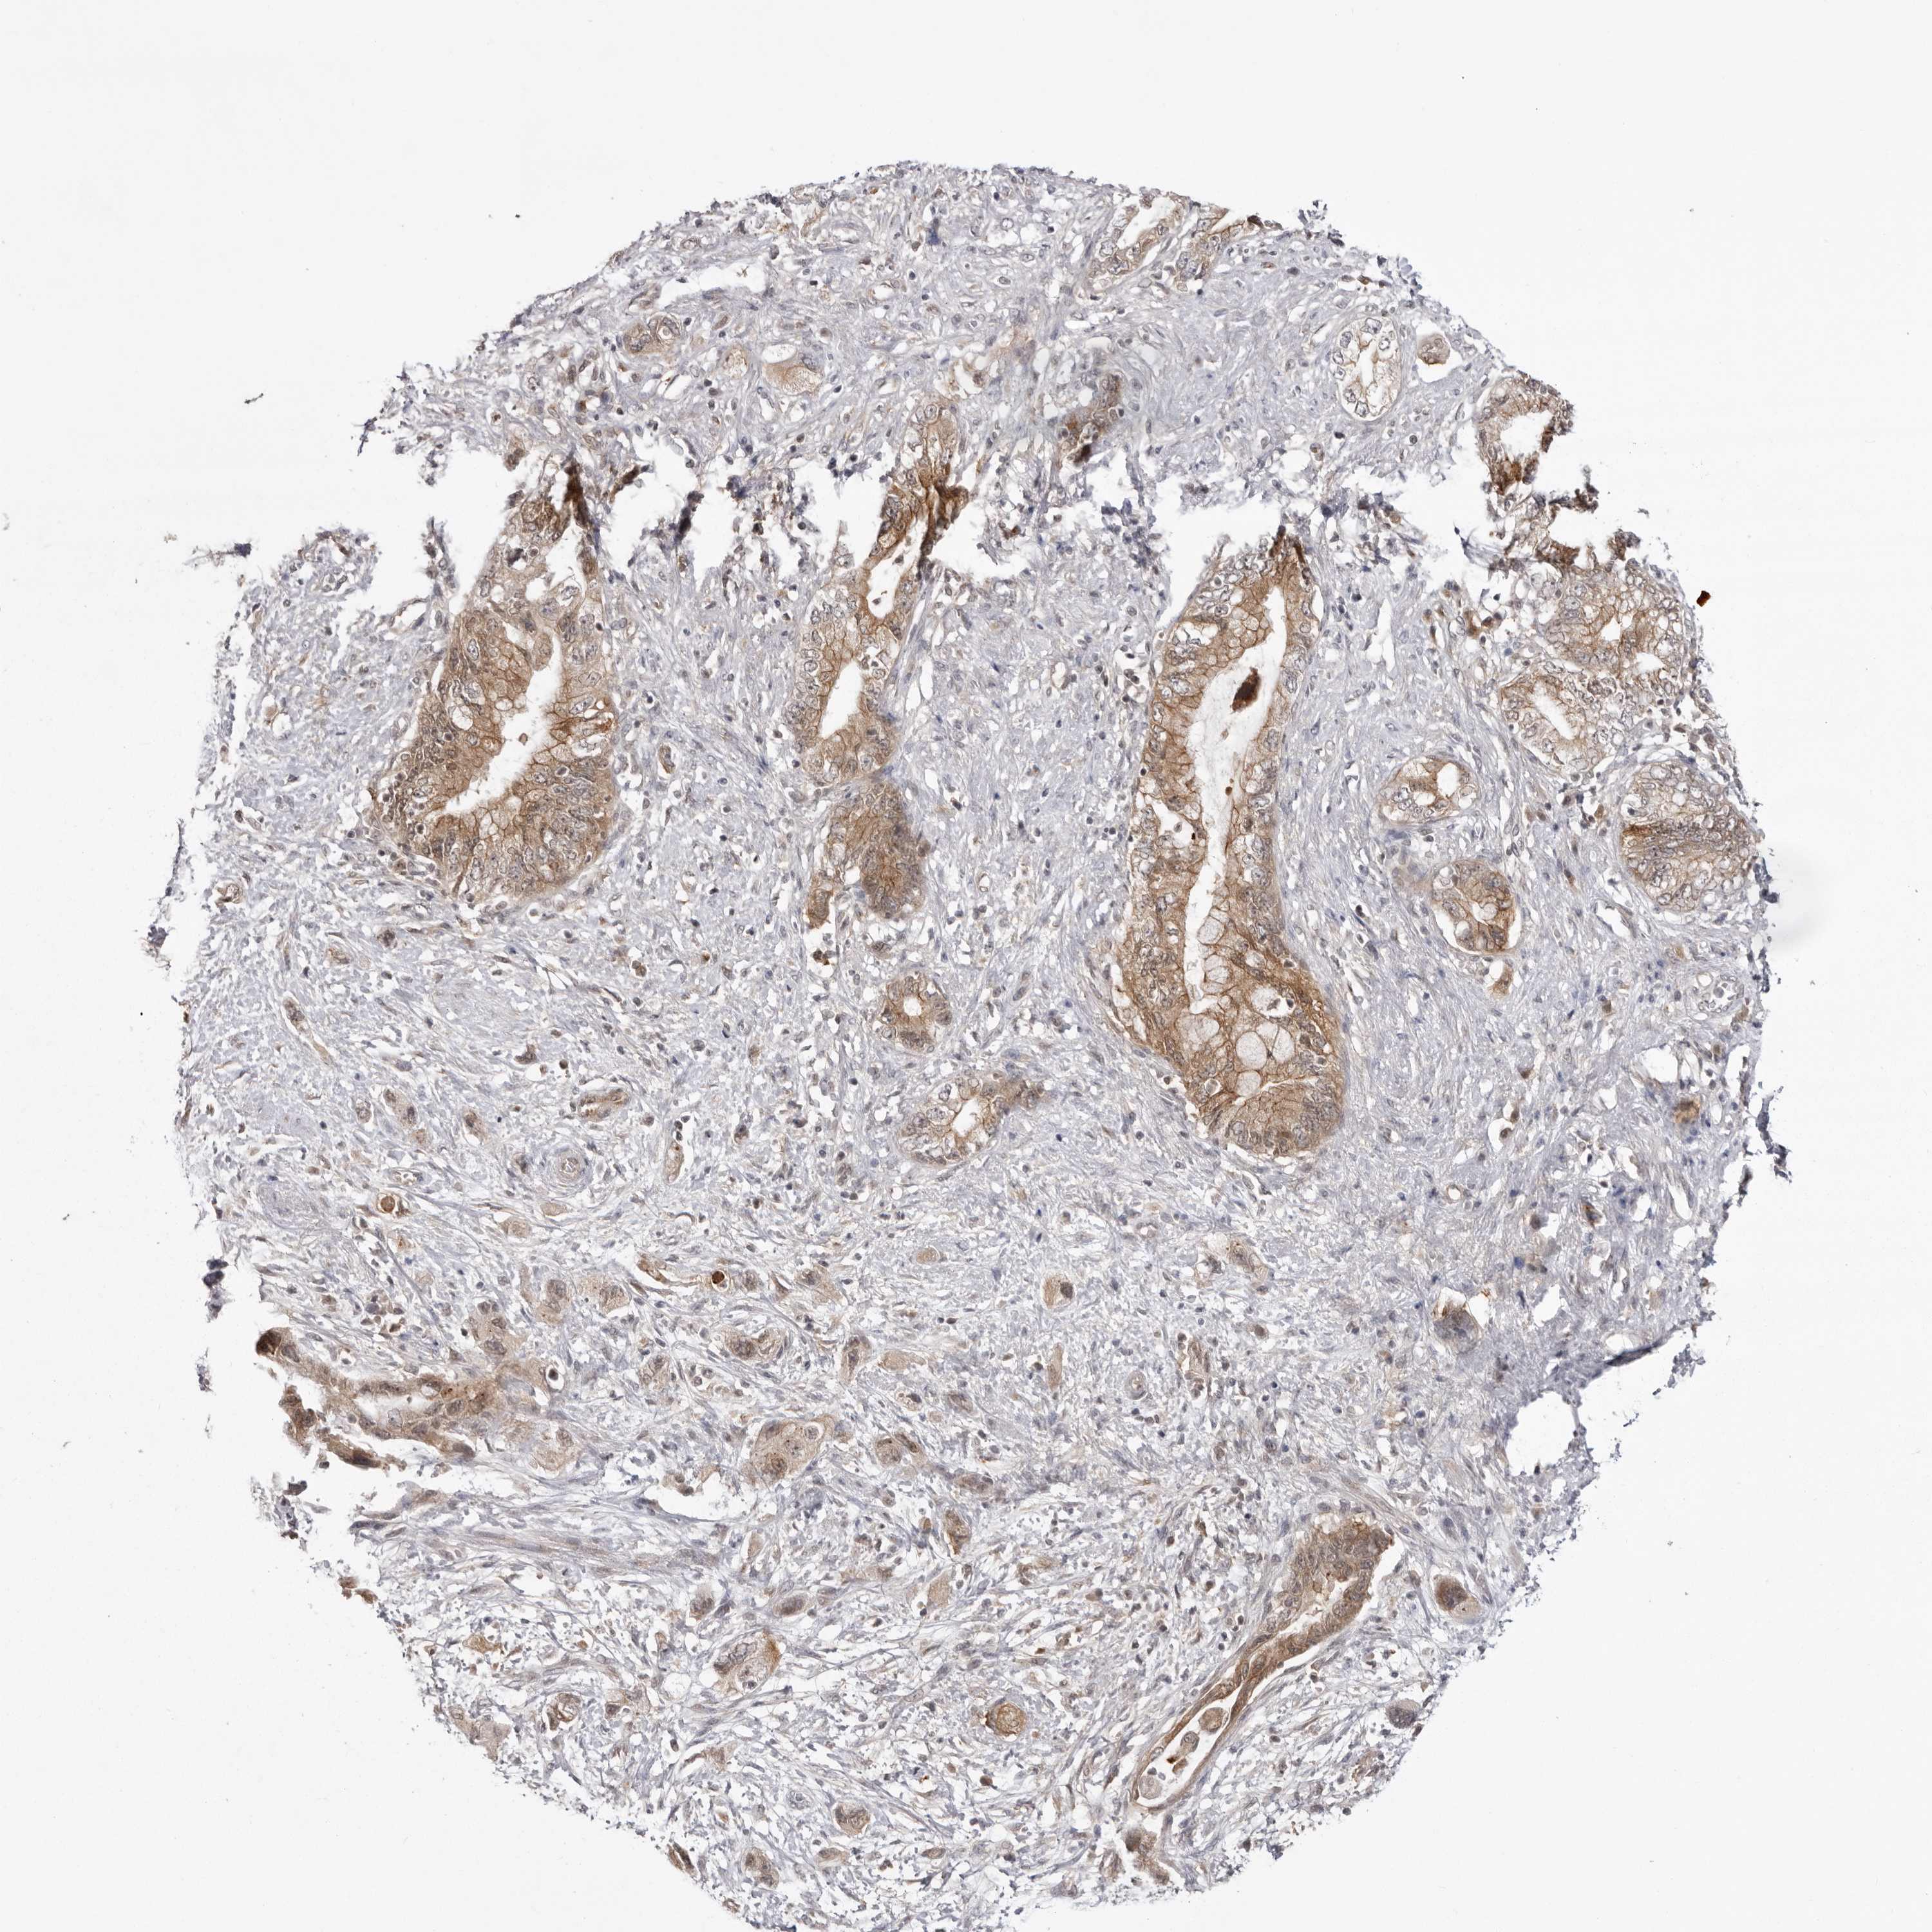

PANCREATIC CANCER - Protein expressioni

A mouse-over function shows sample information and annotation data. Click on an image to view it in a full screen mode. Samples can be filtered based on level of antibody staining by selecting one or several of the following categories: high, medium, low and not detected. The assay and annotation is described here.

Note that samples used for immunohistochemistry by the Human Protein Atlas do not correspond to samples in the TCGA dataset.

Antibody stainingi

Antibody staining in the annotated cell types in the current human tissue is reported as not detected, low, medium, or high, based on conventional immunohistochemistry profiling in selected tissues. This score is based on the combination of the staining intensity and fraction of stained cells.

Each image is clickable and will lead to virtual microscopy that enables deeper exploration of all samples and also displays staining intensity scores, fraction scores and subcellular localization as well as patient and tissue information for each sample.

Antibody HPA023389

Antibody HPA027762

Staining

High

Medium

Low

Not detected

Intensity

Strong

Moderate

Weak

Negative

Quantity

>75%

75%-25%

<25%

None

Location

Nuclear

Cytoplasmic/membranous

Cytoplasmic/membranous,nuclear

Adenocarcinoma, NOS